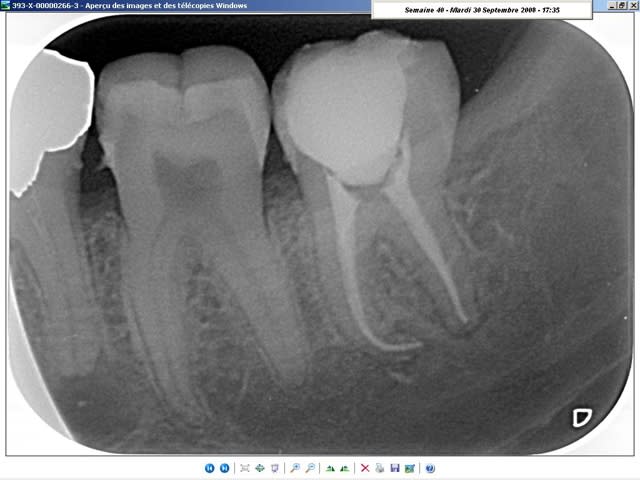

radiologiquement, je ne vois pas trop de différences. A vous de juger.

Les deux cas sont de cette semaine, celui du condenseur, tout frais de cet après-midi; La gutta doit encore être tiède... lol ;-)

sur ce coup, j'étais bien content d'avoir le thermafill (en prêt)!

j'ai préféré faire l'endo plutôt que de galérer à la virer... ^^